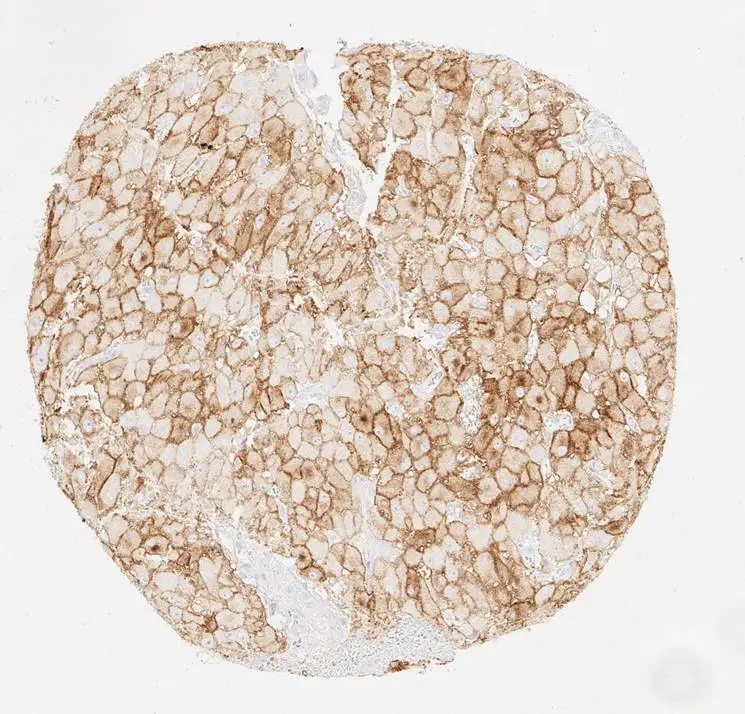

IHC-P analysis of human corpus luteum from ovary tissue using GTX639925 PD-L1 antibody [H302] HistoMAX™.

Moderate to strong membranous PD-L1 staining of corpus luteum cells.